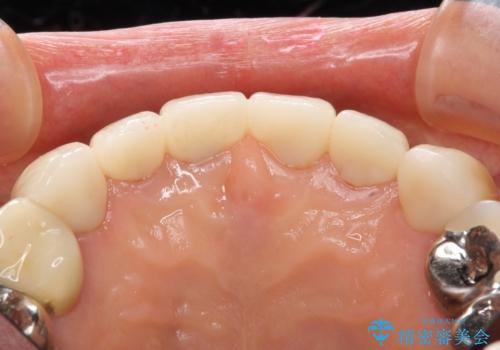

4年半前のクラウン装着時と変わらず、まるで天然歯のように自然に見えました。

患者様の良好なセルフケアと精密な適合の良いクラウンにより、歯肉の腫脹や退縮も認められませんでした。

クラウンの種類:オールセラミッククラウン エコノミー